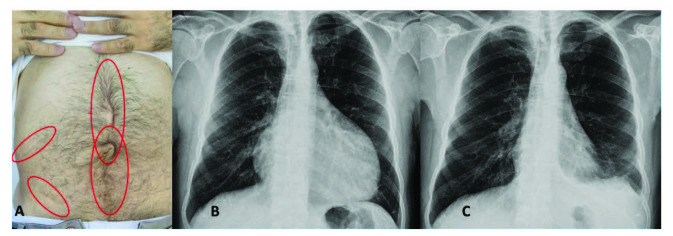

腹膜發(fā)作開(kāi)始局限并迅速蔓延至整個(gè)腹部。腹膜炎癥會(huì)導(dǎo)致典型的腸梗阻癥狀,患者會(huì)遭受?chē)?yán)重的胃痛。體格檢查顯示腹部肌肉僵硬、反跳痛和腸鳴音消失——臨床上這種緊急情況與急腹癥的手術(shù)原因無(wú)法區(qū)分。因此,隱匿性腹部手術(shù)史在良性陣發(fā)性腹膜炎患者中很常見(jiàn)(圖 1A)。在疑似病例中,影像學(xué)檢查可能有助于排除手術(shù)病理。腹部發(fā)作后可能會(huì)出現(xiàn)輕度反彈性腹瀉。盡管有戲劇性的表現(xiàn),但腹膜炎的所有體征和癥狀在 24-72 小時(shí)內(nèi)有效消退,沒(méi)有后遺癥,盡管慢性腹水和腹膜粘連的報(bào)道很少。

包含圖片、插圖等的外部文件。對(duì)象名稱(chēng)為 turkjmedsci-50-1591-fig001.jpg

圖1:(A) 一位因多次腹部手術(shù)而留下疤痕的患者,(B) 胸部 X 光片顯示大量心包積液,(C) 同一患者用阿那白滯素治療后的胸部 X 光片。

心包炎是一種罕見(jiàn)病癥,見(jiàn)于 1%–2% 的患者。心包炎會(huì)出現(xiàn)胸骨后胸痛和呼吸困難等癥狀。心包填塞可能很少發(fā)生。心電圖顯示 ST 段抬高,胸部 X 光片可能顯示心臟輪廓的短暫擴(kuò)大(圖 1B 和 1C),超聲心動(dòng)圖顯示心包積液。在極少數(shù)情況下,反復(fù)性心包炎可能是良性陣發(fā)性腹膜炎的少有表現(xiàn),這可能與特發(fā)性心包炎相混淆 。